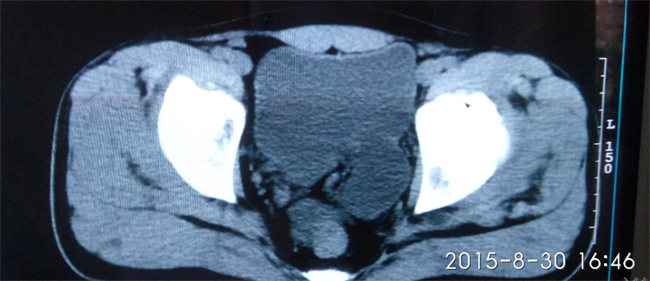

女性尿道旁囊肿,又称为Bartholin腺囊肿,是一种较为常见的妇科疾病。其主要原因是尿道旁腺出口被阻塞,导致腺内分泌物积聚形成囊肿。一些因素可能会导致Bartholin腺阻塞,如感染、损伤或其他疾病等。下面将介绍Bartholin腺囊肿的原因及护理方法。...

女性尿道旁囊肿,又称为Bartholin腺囊肿,是一种较为常见的妇科疾病。其主要原因是尿道旁腺出口被阻塞,导致腺内分泌物积聚形成囊肿。一些因素可能会导致Bartholin腺阻塞,如感染、损伤或其他疾病等。下面将介绍Bartholin腺囊肿的原因及护理方法。